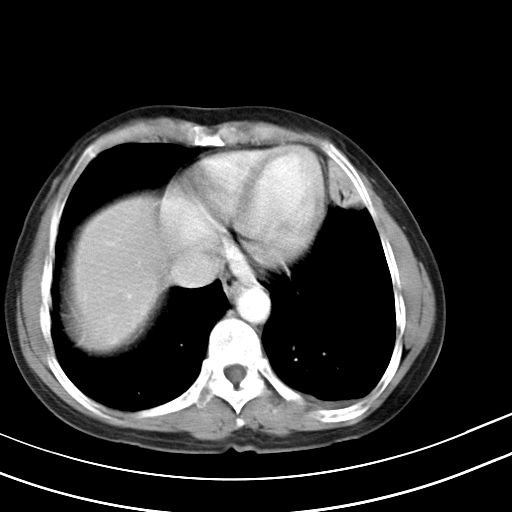

考虑两肺炎症,左胸腔积液,建议治疗后复查!

考虑炎性病变,左肺舌叶病灶需要与早期肺脓肿鉴别(结合实验室),左侧少量胸腔积液。

考虑两肺炎症,建议治疗后复查,左侧少量胸腔积液

1)右肺上叶前段及左肺上叶舌段感染性病变;建议抗炎治疗后复查。2)左侧少量胸腔积液。